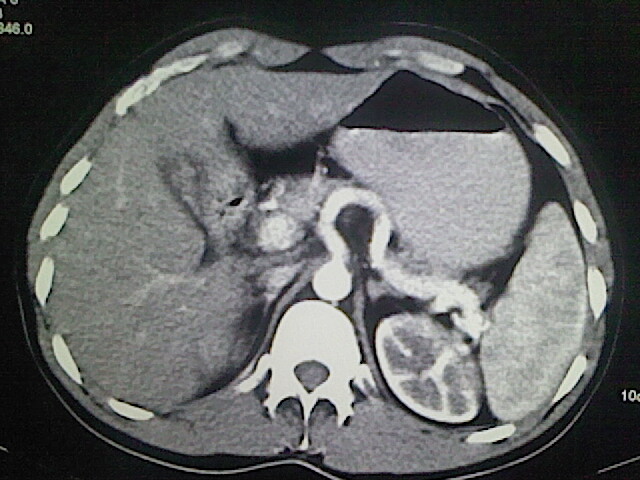

以下是引用卜一在2009-3-14 9:49:00的发言:[br]胆囊萎缩,胆囊壁不规则增厚,内部结构模糊,增强明显强化。另:肝左叶外侧段肝囊肿。支持:慢性胆囊炎!高度可疑:胆囊癌!

以下是引用余辉在2009-3-14 8:48:00的发言:[br]1)慢性胆囊炎。2)肝左叶外侧段肝囊肿。3)脂肪肝。[br]支持,胆囊萎缩,密度增高,不知b超具体有何提示,钙胆汁?结石?

以下是引用jiangjing在2009-3-14 10:18:00的发言:[br]1)慢性胆囊炎。2)肝左叶外侧段肝囊肿。3)脂肪肝。4.】建议行肝功能检查